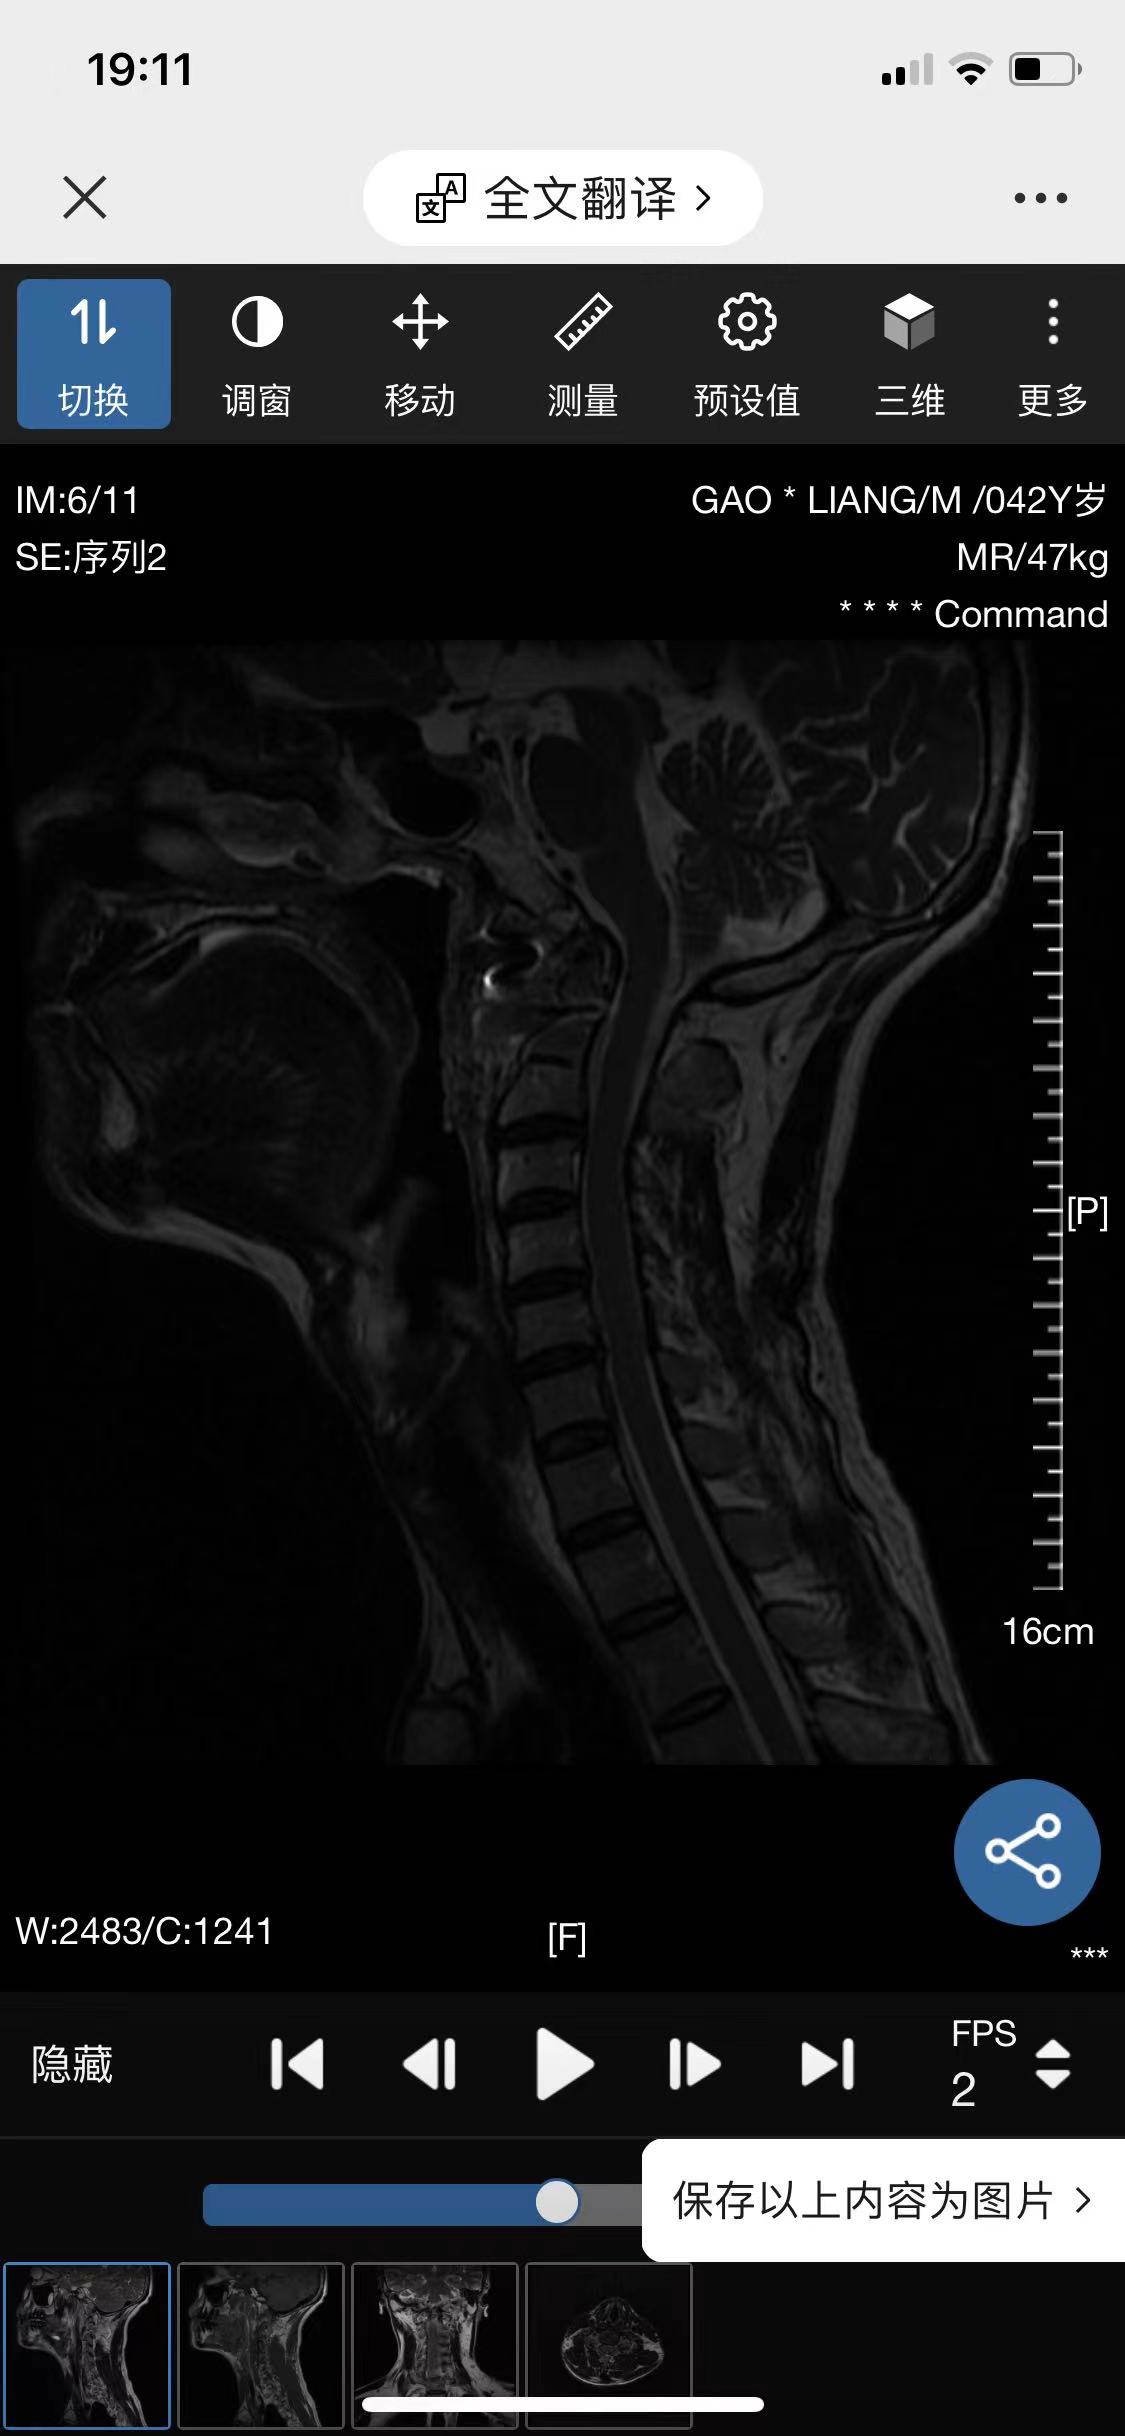

• 诊断:寰枢椎脱位

• 术后影像: